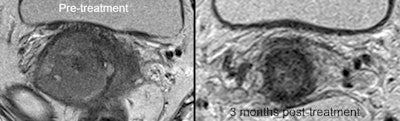

33-year-old LACC patient with stage 2B disease, node negative. MRI was performed 86 days after completion of conformal radiation therapy. Score grade 1 was recorded, indicating complete response. All images courtesy of Prof. Andy Scarsbrook.

33-year-old LACC patient with stage 2B disease, node negative. MRI was performed 86 days after completion of conformal radiation therapy. Score grade 1 was recorded, indicating complete response. All images courtesy of Prof. Andy Scarsbrook. FDG-PET/CT in the same patient shows primary tumor, SUVmax 11.5. FDG-PET/CT scan performed 94 days after completion of CRT gave score of grade 4, indicating patient metabolic response.